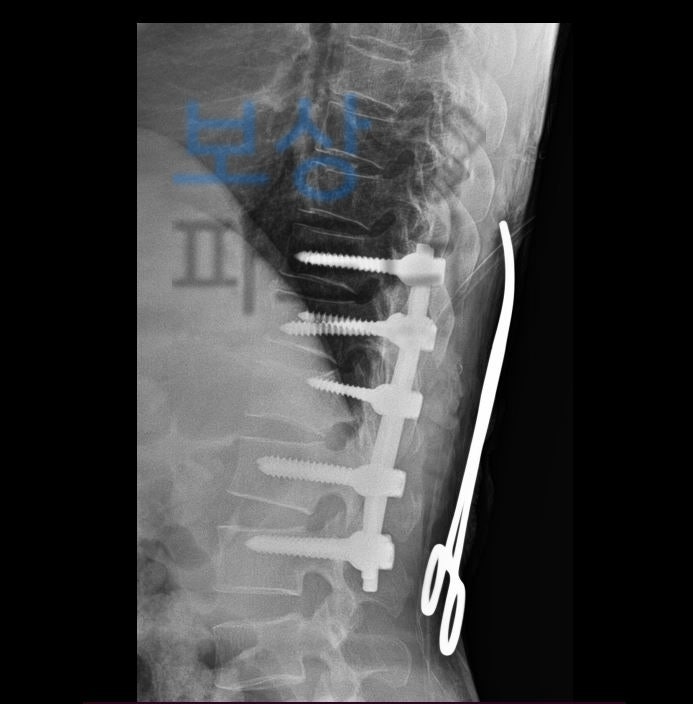

흉추, 요추 후방 유합술 (고정술) 산재 장애등급 7급 손해보험 보상 심각한 척추 골절로 안정성 확보를 위해 흉추10번 부터 요추2번 까지 후방 유합술 즉 수술적 치료를 받으셨습니다.

Spinal fixation of T10~L2

하지만 한@@님은 수술 이후 다리를 움직일 수 없었고 근전도 검사 결과 상 하반신 마비 판정을 받게 되었죠.